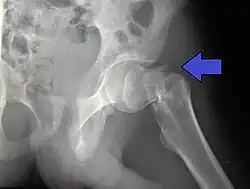

X-rays of the affected hip usually make the diagnosis obvious; AP (anteroposterior) and lateral views should be obtained.

In elderly patients with displaced or intracapsular fractures surgeons may decide to perform a hemiarthroplasty, replacing the broken part of the bone with a metal implant.[39] However, in elderly people who are medically well and still active, a total hip replacement may be indicated. Independently mobile older adults with hip fractures may benefit from a total hip replacement instead of hemiarthroplasty.[40]